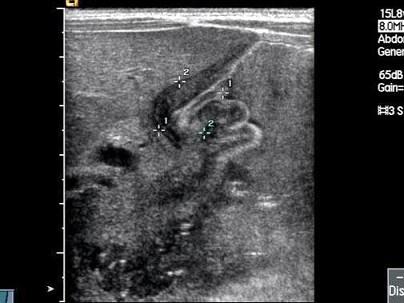

问题 患儿,出生1个月,因喂奶时经常呕吐,加重数天就诊,婴儿明显消瘦,皮肤松弛有皱纹,皮下脂肪减少,精神抑郁呈苦恼面容。喂奶时,可见从左季肋向右上腹移动之蠕动波。根据超声示意图,最可能的诊断为?(?)

选项 A.先天性肥厚型幽门狭窄 B.先天性胆管狭窄 C.胃溃疡 D.肠炎 E.肠梗阻

答案 A